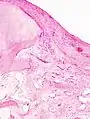

Histopathology of osteoarthrosis of a knee joint in an elderly female